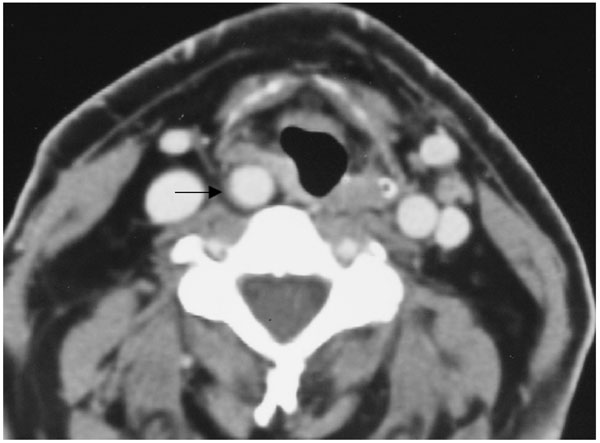

Right aberrant cervical internal carotid artery promotes focal pharyngeal bulging (patient #4).

Axial enhanced CT scan t throughout the supraglottic level shows aberrant right ICA causing focal bulging at the level of the right pyriform sinus with right aryepiglottic fold displacement (arrow). (Radiological classification of this patient was considered C,1).